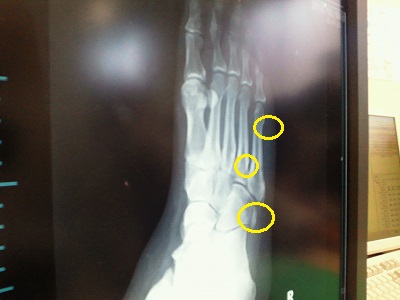

足回り点検の結果

右足小指と薬指など三か所が骨折していました。

・・・あれれ?